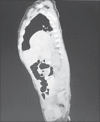

Figure 3

Computed tomography of the thorax (sagittal section) suggesting left posterior diaphragmatic defect with herniation of the stomach, spleen and bowel in the left hemithorax